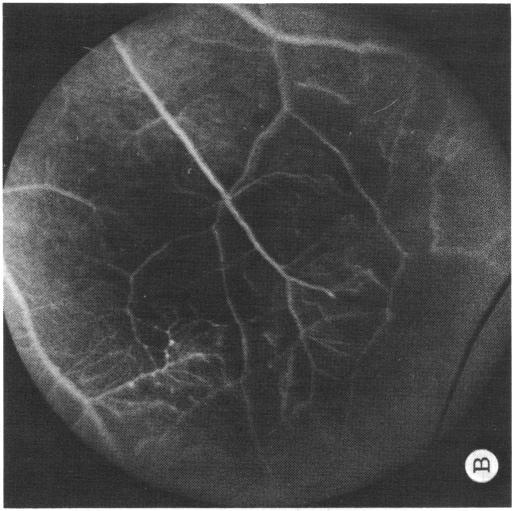

Coats' disease and congenital vascular retinopathy.

Trans Am Ophthalmol Soc. 1976;74:365-424.